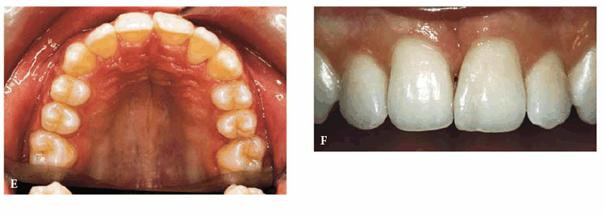

RESULT: The team work of several specialists created a good

morphic-functional recovery (Figures 27-11E and F) and an esthetic result that satisfied

the patient (Figures 27-11G and H).

Figure 27-11E and F: The morphic-functional recovery at the end of the orthodontic treatment.

Figure 27-11G and H: The final result showing the patient's smile at the end of the treatment.